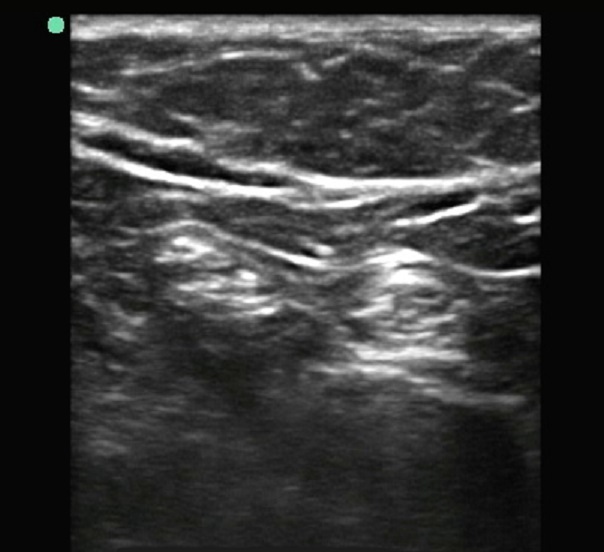

Imagen de la bifurcación del nervio poplíteo